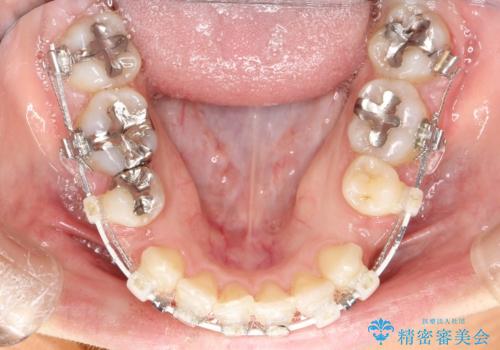

- 審美装置

- 2年2ヶ月

- 10-30回